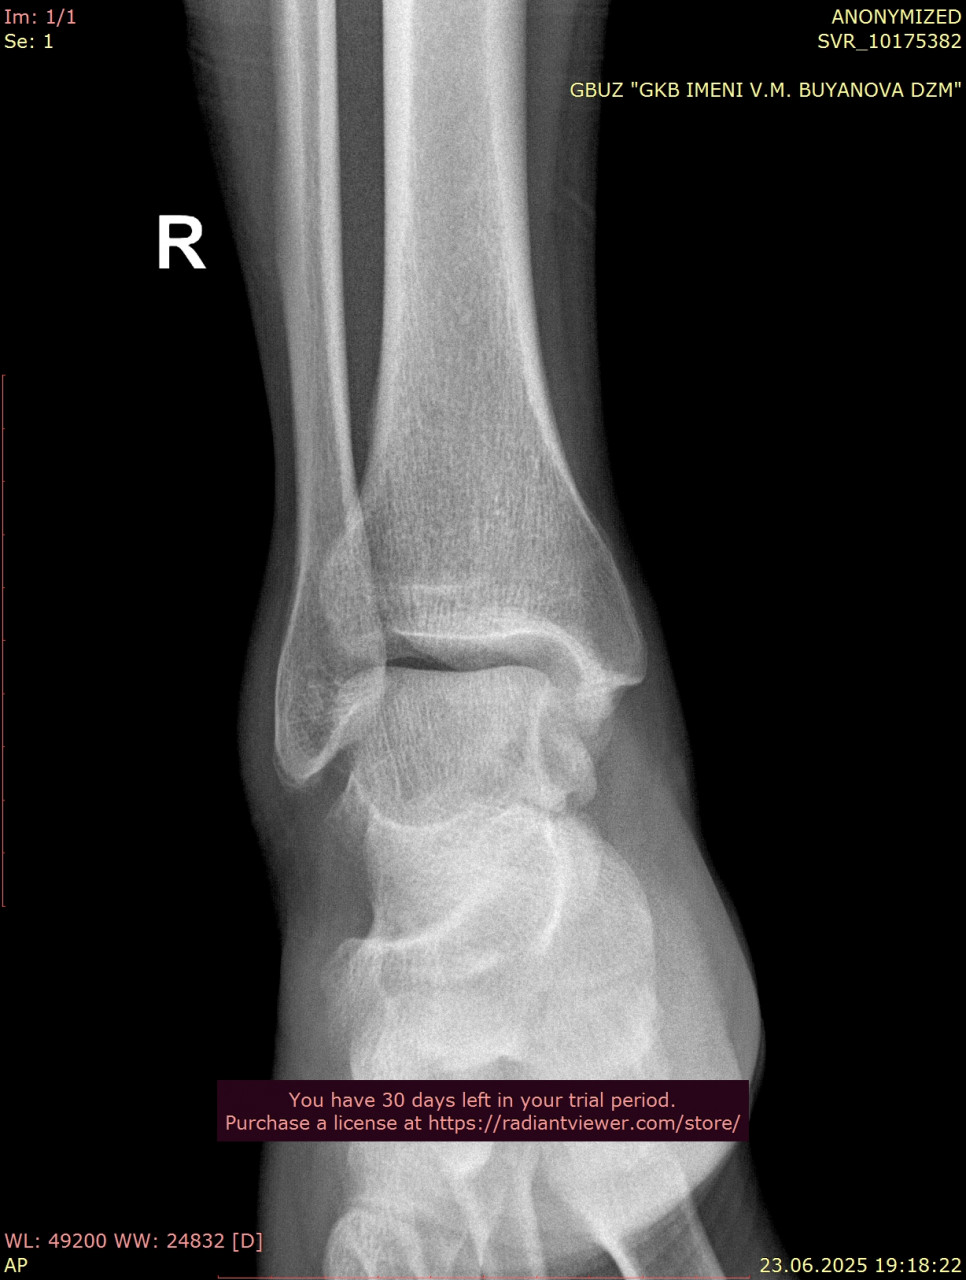

Прикрепляю снимки лодыжки от 23.06.2025, когда был перелом

Сравнивая ваши снимки от 23.06 и 25.08:

- Линии переломов на костях стопы и области голеностопного сустава больше не прослеживаются чётко, видна формирующаяся костная мозоль – это признак заживления.

- Смещения отломков нет, контуры выровнены, что говорит о правильном срастании.

- Для срока 2 месяца после перелома динамика положительная, основные признаки консолидации присутствуют. Обычно к этому времени разрешают постепенную нагрузку, но полное снятие опоры (ходьба без костылей, тростей) должно быть постепенным и согласовано с вашим травматологом.

По поводу артроза, на рентгене действительно заметны начальные изменения в суставах стопы (сужение суставных щелей, небольшие краевые разрастания), но они умеренные и для 38 лет не критичны. Такие изменения часто встречаются после травм и нагрузок, но выраженного деформирующего артроза нет.